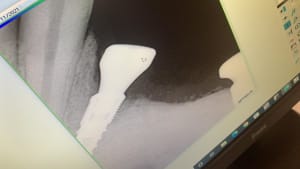

Implant 34 ETK 3,5 12mm.jpg